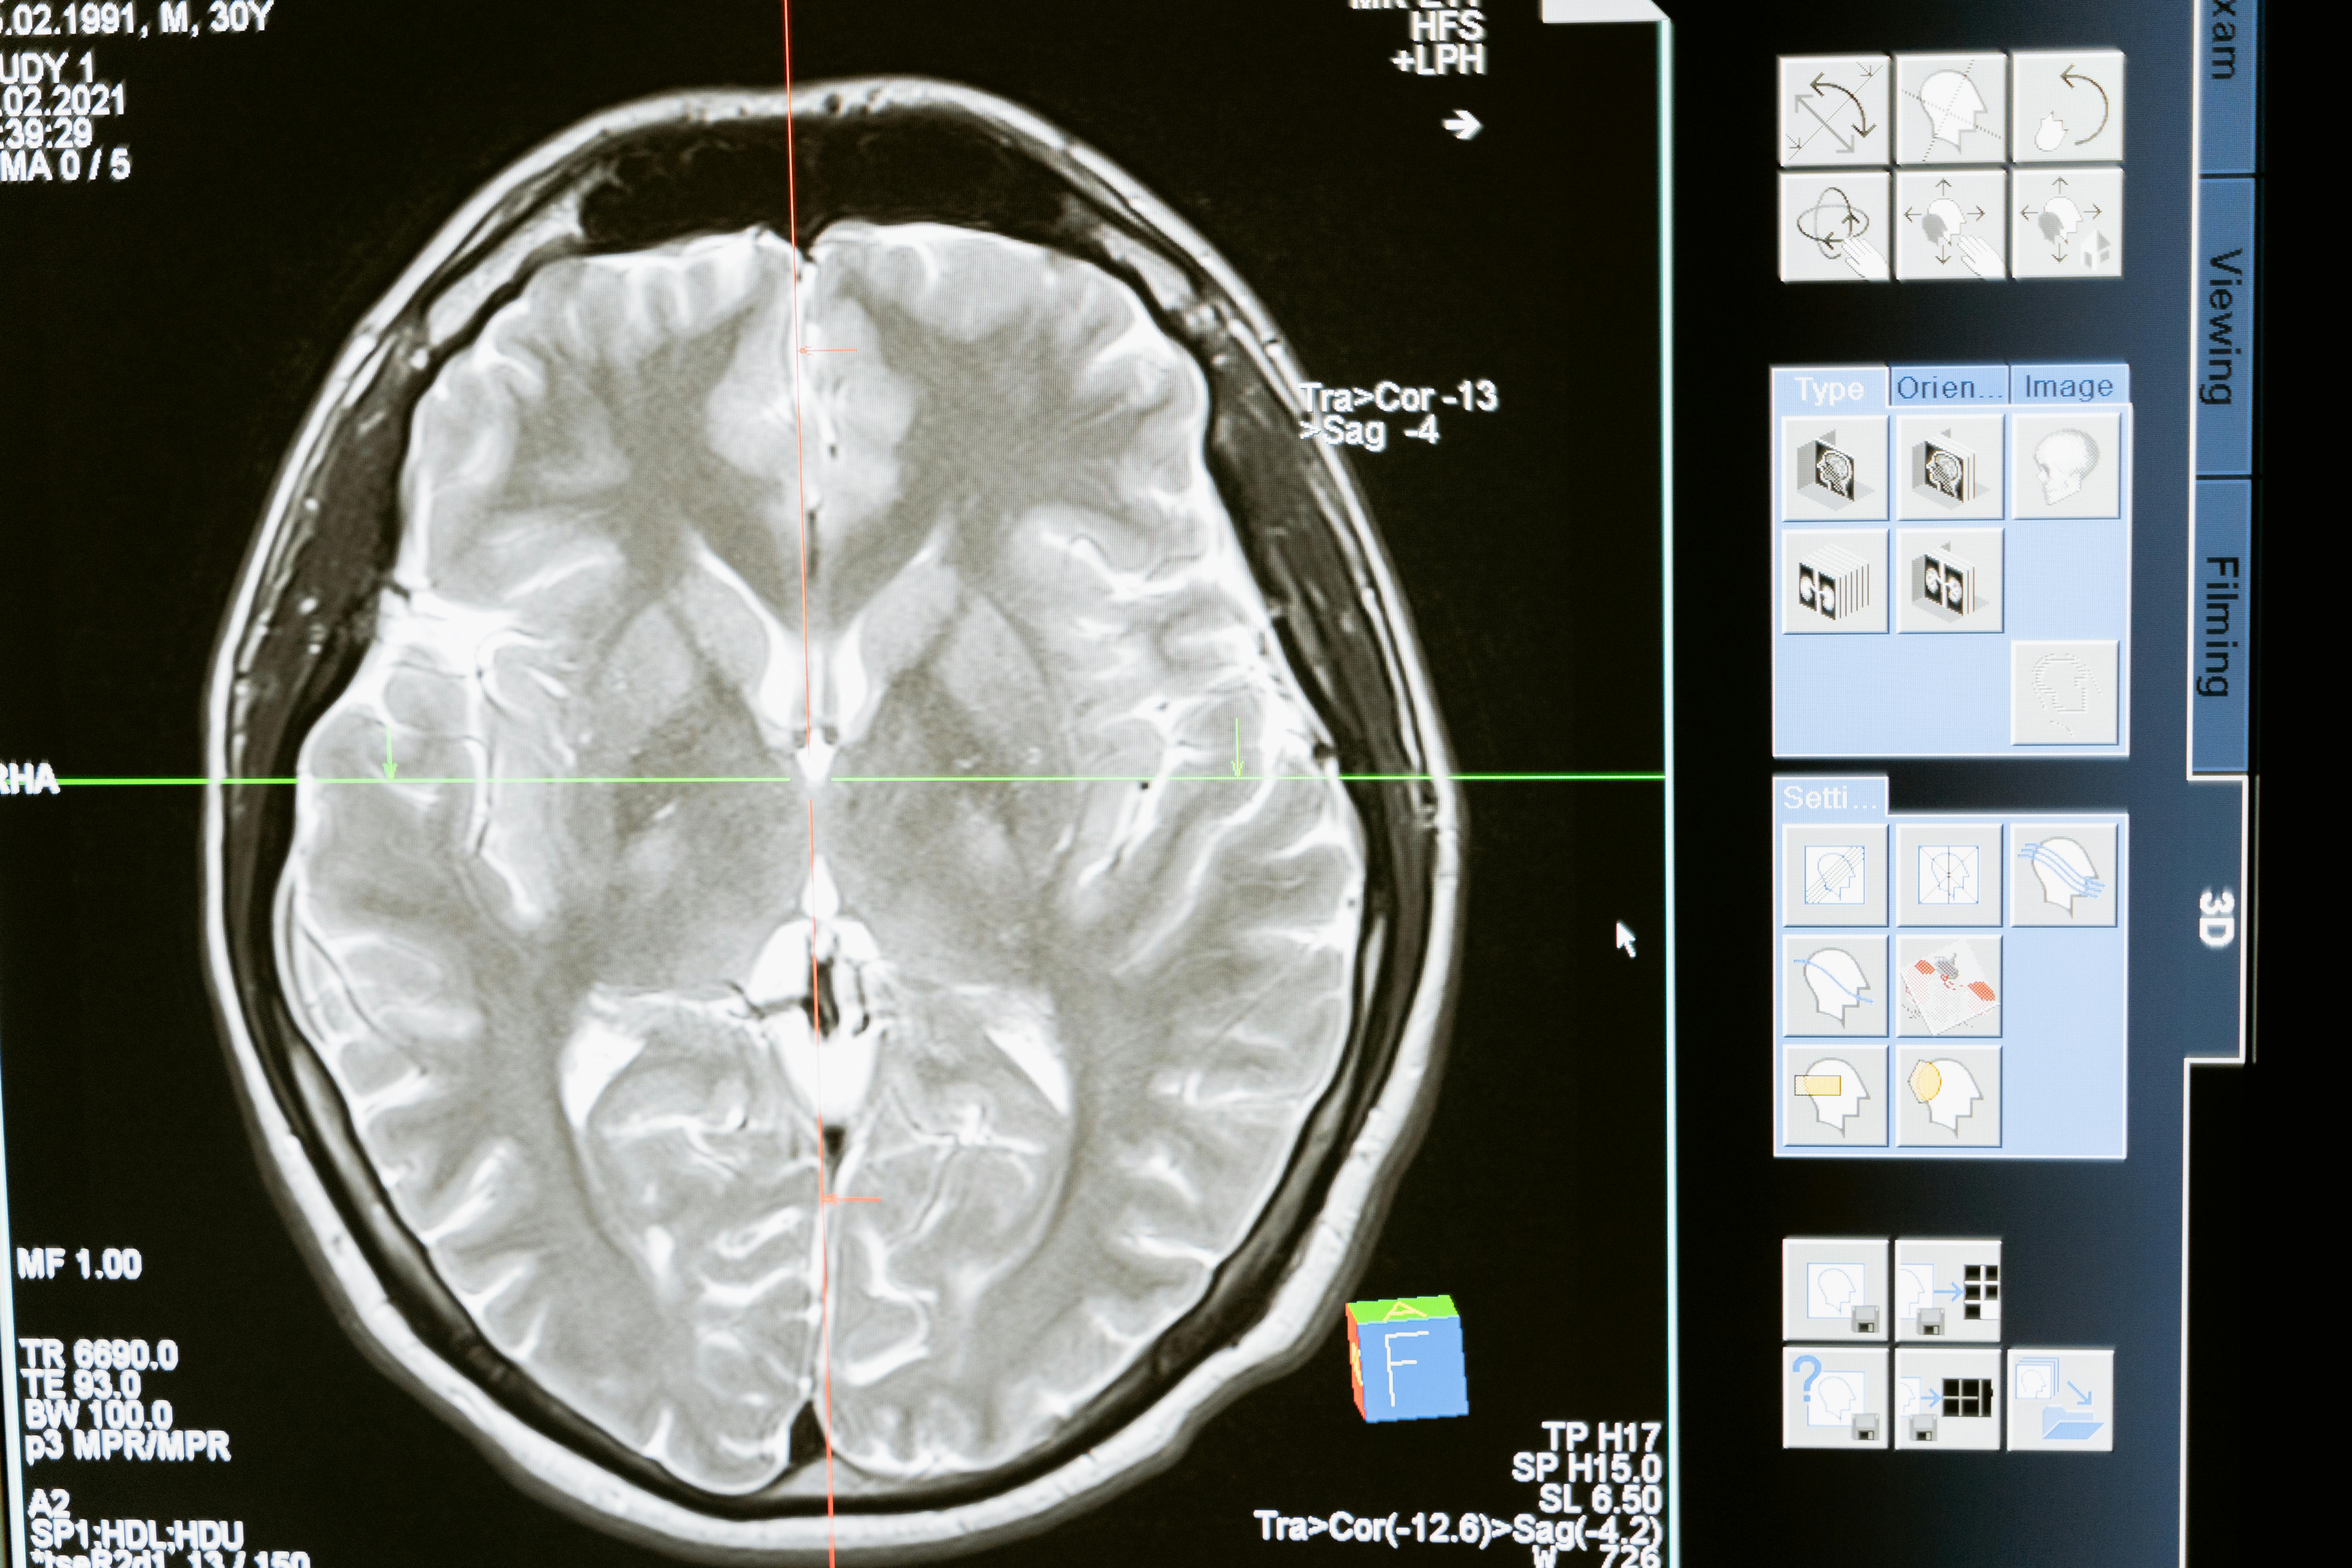

Una de las pruebas clave es la resonancia magnética, que permite ver con precisión el cerebro y la médula espinal y buscar lesiones típicas de la esclerosis múltiple. En algunos casos también se recomienda una punción lumbar para analizar el líquido cefalorraquídeo y buscar datos que apoyen el diagnóstico. Otras pruebas complementarias, como los potenciales evocados o análisis de sangre, ayudan a descartar otras causas que puedan explicar los síntomas.

Es importante saber que el proceso diagnóstico puede llevar tiempo. A menudo se necesita seguimiento con nuevas visitas y resonancias magnéticas para confirmar la enfermedad y asegurarse de que se cumplen los criterios internacionales de esclerosis múltiple. Este tiempo no significa que se esté perdiendo oportunidad de tratamiento, sino que se busca la máxima seguridad y precisión antes de etiquetar el diagnóstico.